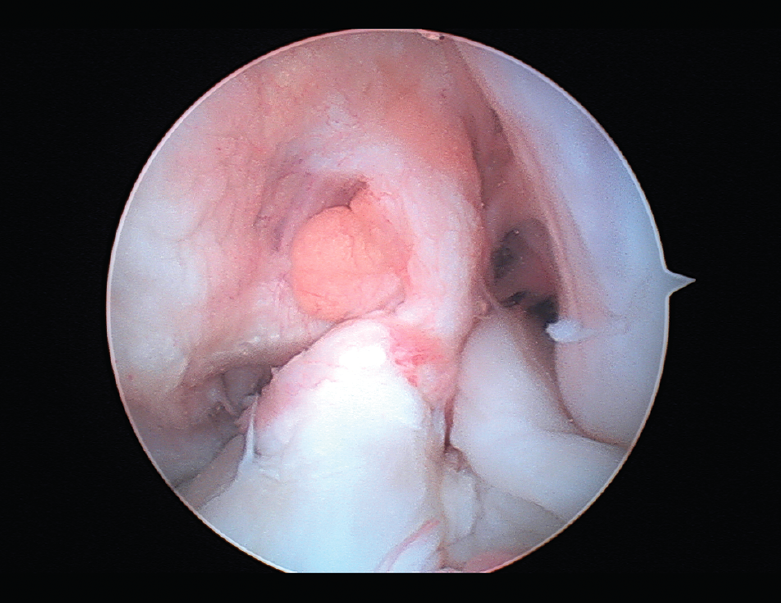

Figura 2. Rotura aguda del ligamento cruzado anterior.

El tratamiento de un paciente que sufre una rotura aguda del LCA (Figura 2) sigue siendo motivo de discusión(9). Hay muchos condicionantes que influyen en el manejo terapéutico de estas lesiones (ya sea quirúrgico como no quirúrgico), como son la edad, la ocupación, la actividad deportiva, las lesiones asociadas, el grado de laxitud de la rodilla, las expectativas o las recidivas de la lesión, entre otras. El riesgo de artrosis tras la rotura aguda del LCA será mayor en ambos grupos con respecto a la población sana, sea cual sea el tratamiento(12). Los factores de riesgo más importantes para el desarrollo de artropatía son: lesión meniscal, meniscectomía e injerto hueso-tendón-hueso (HTH).